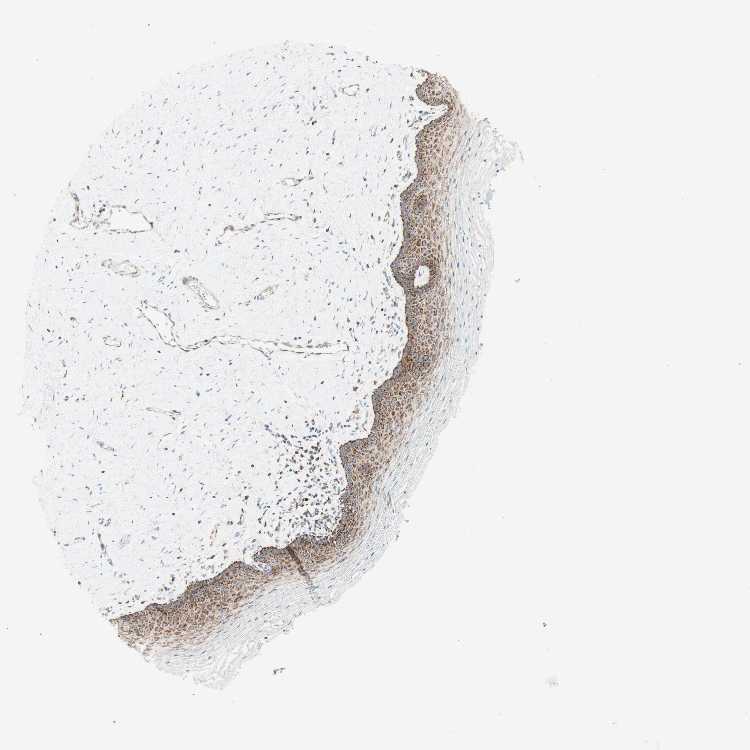

TISSUE PRIMARY DATA VAGINA Show tissue menu

VAGINA - Antibody stainingi

Antibody staining in the annotated cell types in the current human tissue is reported as not detected, low, medium, or high, based on conventional immunohistochemistry profiling in selected tissues. This score is based on the combination of the staining intensity and fraction of stained cells.

Each image is clickable and will lead to virtual microscopy that enables deeper exploration of all samples and also displays staining intensity scores, fraction scores and subcellular localization as well as patient and tissue information for each sample.

Antibody HPA011562Antibody CAB005585

Squamous epithelial cells HighHigh